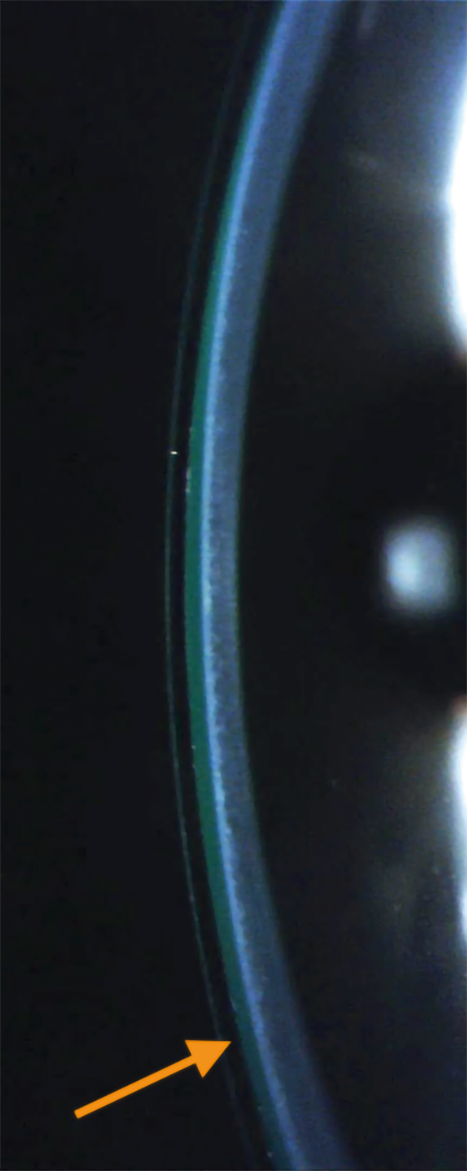

At the second lens dispense and follow up, the patient achieved clear and single vision with the 4 pd BD lens OD (Figure 2, Figure 3). The prism was then split into 2 pd base down OD and 2 base up OS to achieve a thinner lens thickness OD from 0.54 mm to 0.38 mm. The vertical landing zone was also steepened to assist in lens centration and rotational stability. The gas permeability of the lens was increased from 100 to 180 as well to compensate for the reduction in oxygen transmittance due to increased lens thickness from the incorporation of prism.

Figure 2: Sclerallens-cornea cross section. Left: OD with base down prism and its increased lens thickness inferiorly (orange arrow) compared to superiorly, right: OS without prism showing a thinner, more uniform lens thickness (orange arrow).